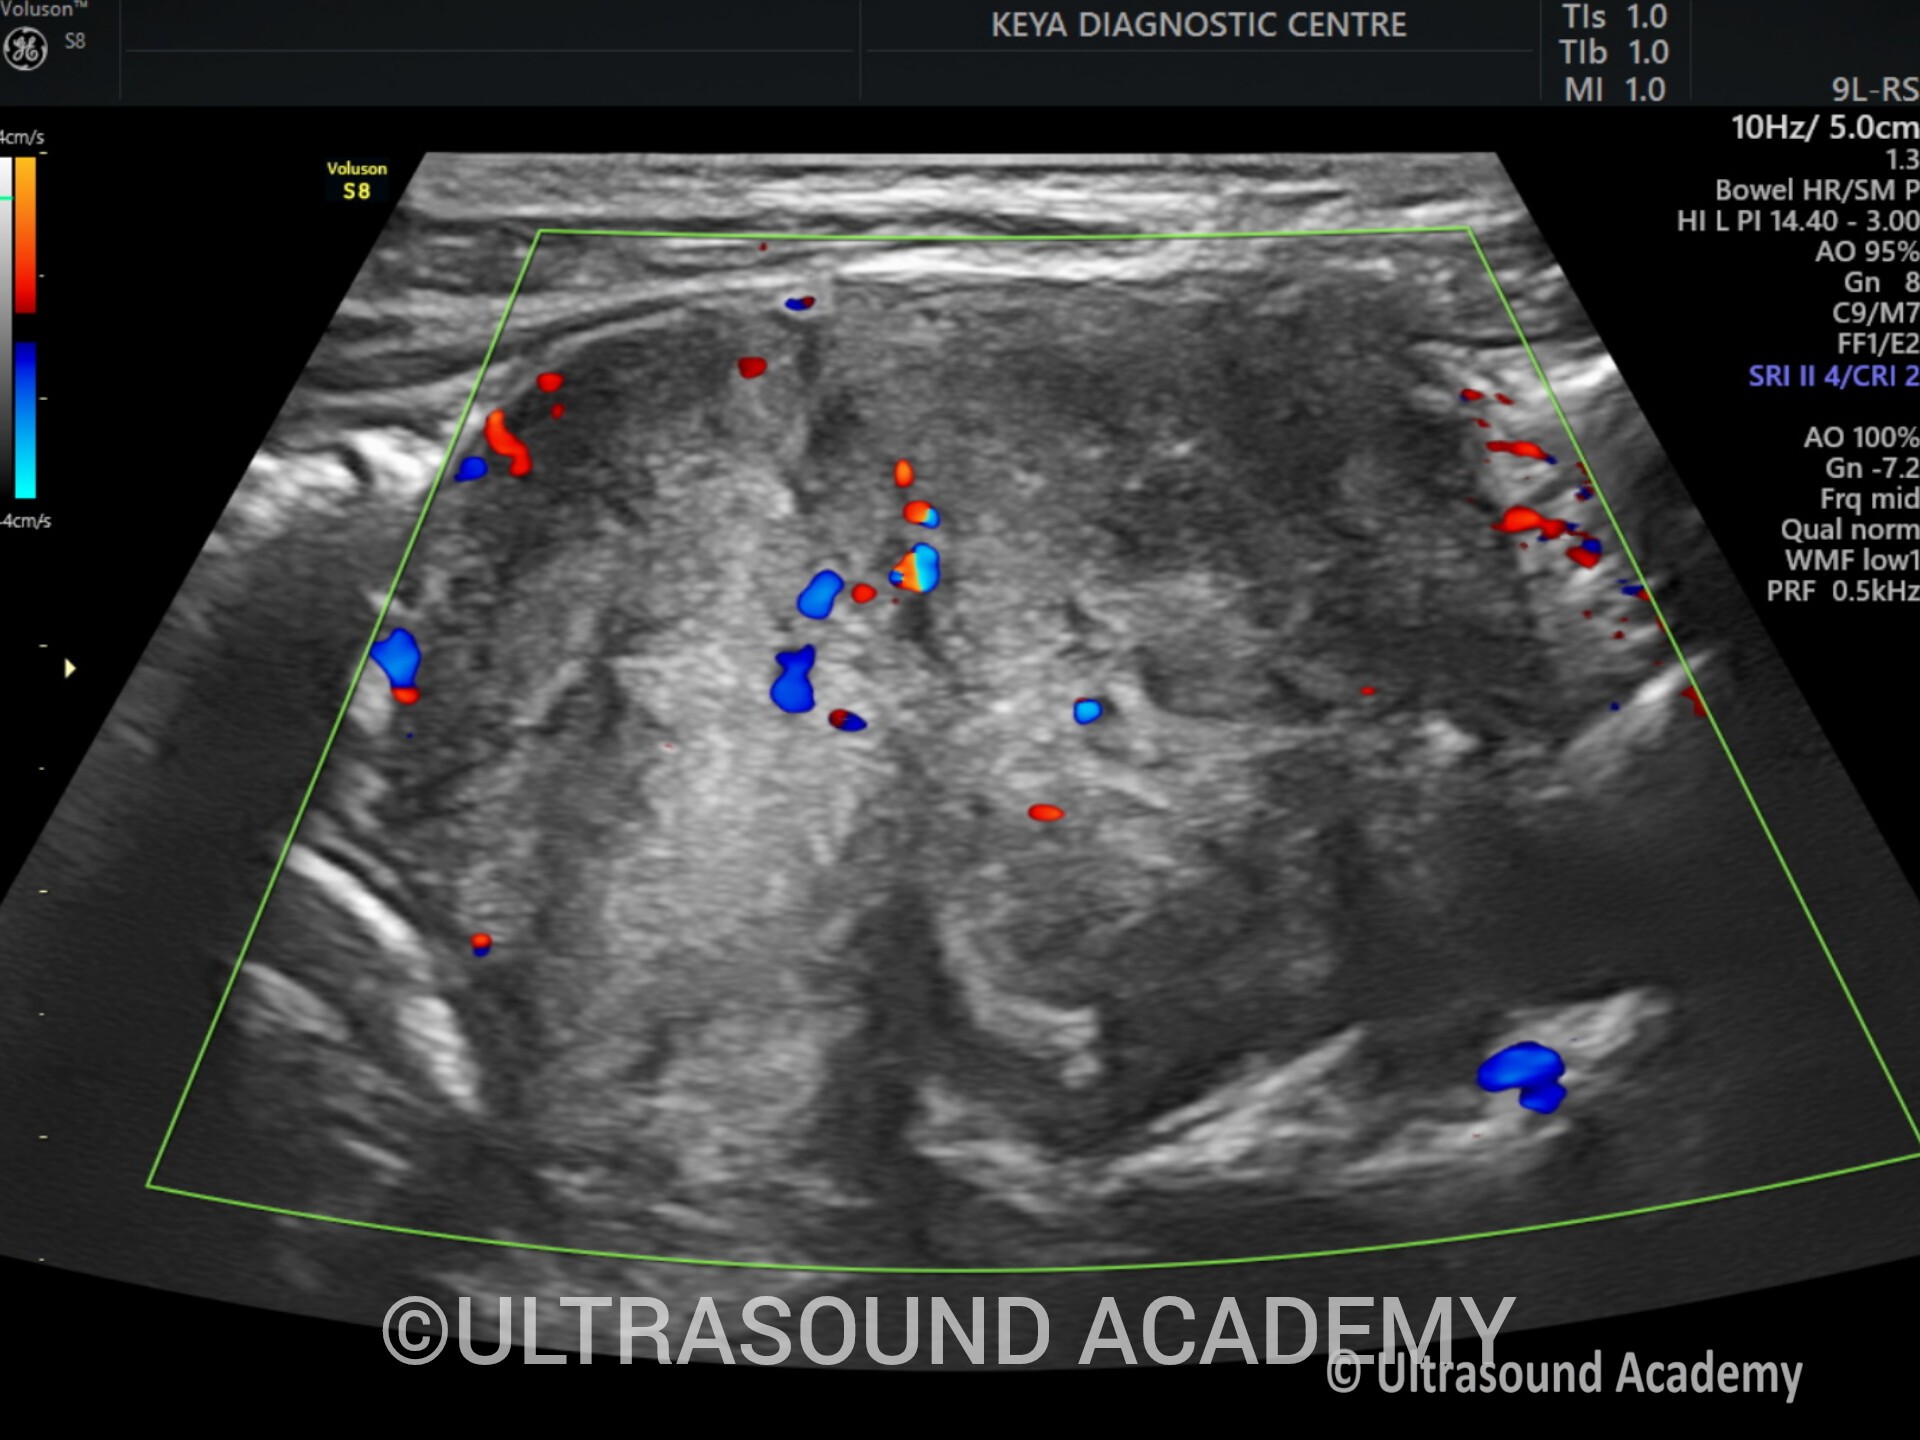

ABDOMINAL ROUND CELL TUMOUR – Case By Dr. Nitin Jadhav